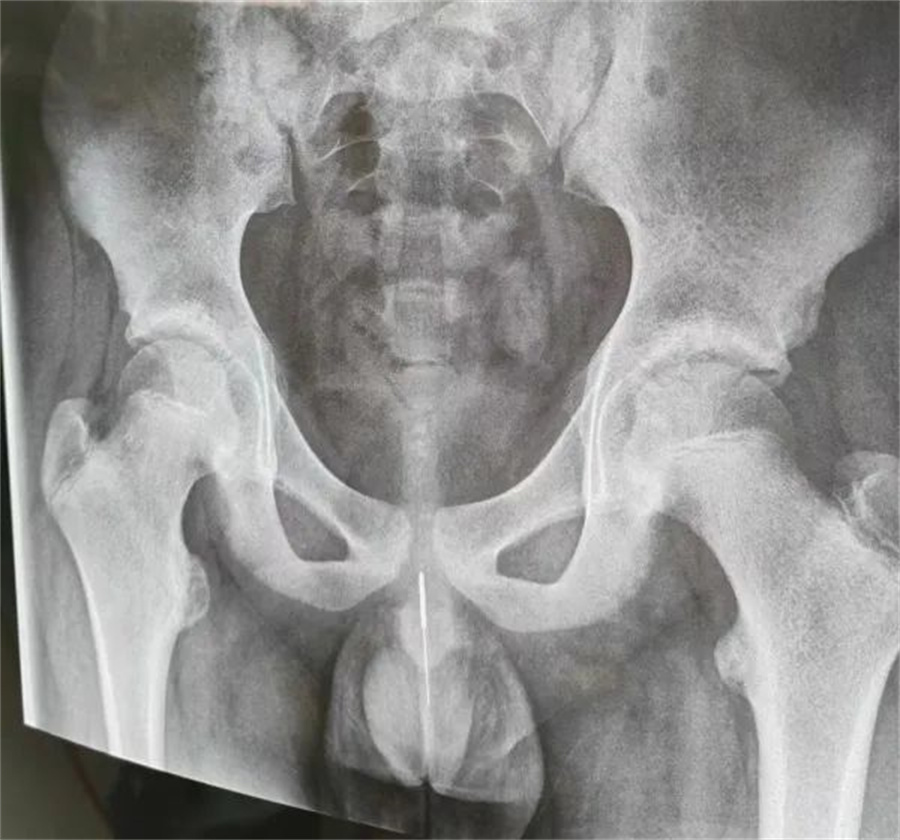

“孩子大概是中午的时候把银针塞进尿道中,因为针灸银针前段柔软纤细而末段又有增粗的螺旋状柄头,所以很难取出来。家长已经带他在当地医院拍片确诊,晚上7点多转到我们医院,当时孩子尿道口有血,疼痛难忍......”啪啪网

急诊外科接诊后立即收入院并第一时间做好手术准备,此时泌尿外科主任谢方达也紧急从家中赶到了医院,经过术前检查,确认银针卡在了接近球部尿道的部位,位置比较深,又没进入到膀胱里,如何尽快地取针成为一个颇具难度的挑战。

孩子家长和泌尿外科专家都希望用最微创的方式完成手术。但因孩子年龄小、尿道细,体重又偏大而难以实现,术中医生在保证对孩子造成伤害最小的前提下,采取隐匿小切口的方式,顺利将6.5cm的银针从尿道中刺破取出,为孩子解除了困扰,术后恢复三四天后即可顺利出院。